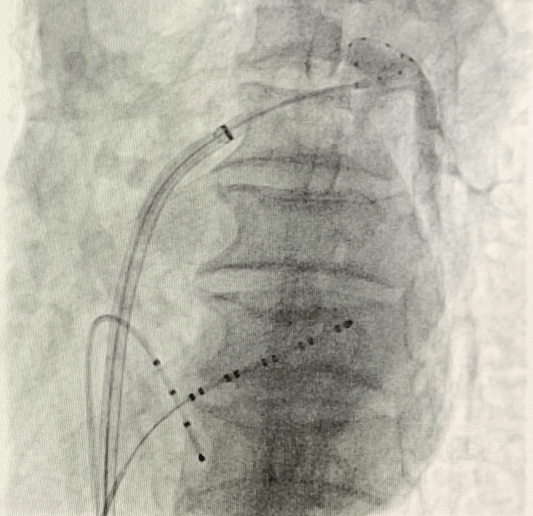

(手術(shù)過(guò)程)